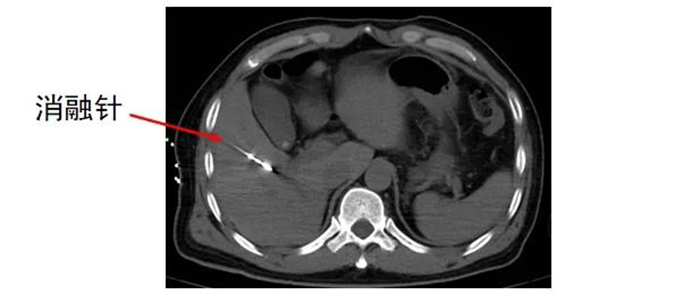

经多学科讨论,齐先生适合转化治疗,首先利用消融的方法解决肝内转移瘤,同时根据病理科基因检测结果进行全身系统治疗,待转化治疗成功,肿瘤缩小、降期后,吻合口复发区域再进行手术切除。 肿瘤科、麻醉手术科 及放射影像科协同合作 为齐先生进行 经皮肝恶性肿瘤微波消融术

经皮肝恶性肿瘤微波消融术是治疗肝脏恶性肿瘤的局部微创治疗方法,具有创伤小、恢复快、对肝功能影响相对较小等优点。

但如何确保在手术中精准定位,将消融针准确置入肿瘤部位,并根据肿瘤的具体情况,合理控制消融范围和能量,避免损伤周围正常组织,需要医生拥有丰富经验和精准操作技巧,以及较强的判断力、把控力。

齐先生病灶临近大血管、重要脏器。跳蛋视频 专家团队在CT引导下精准定位,经皮穿刺将微波消融针准确置入齐先生肝脏肿瘤部位,然后利用微波能量,使肿瘤组织内的水分子快速振动、摩擦产生热量,从而使局部温度迅速升高,让肿瘤细胞凝固性坏死。整个手术过程顺利,避免了严重并发症发生。

准确插入到病灶内,并避开了门静脉左支及分支,避免了出血并发症。

准确插入到病灶内,并避开了门静脉右支及胆,避免了出血、损伤胆囊等并发症。